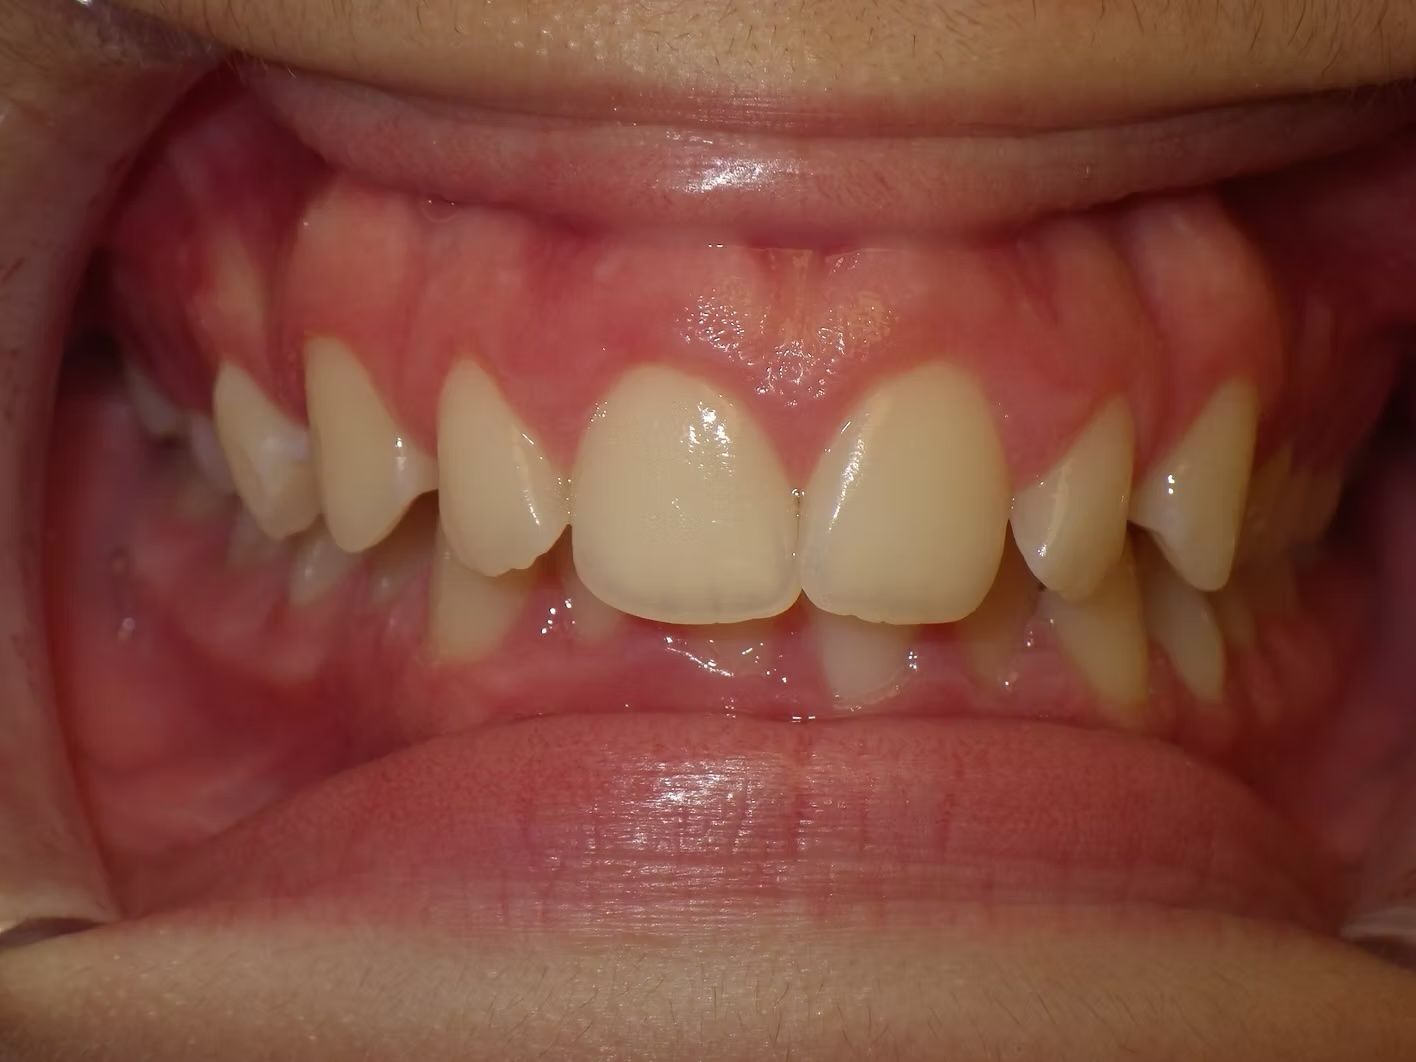

Johntavious

Johntavious didn't like that one of his lower teeth was set behind the rest. He went to many orthodontists who told him to extract the tooth or multiple teeth to correct the alignment. Johntavious and his parents didn't want to go that route and wanted to try to align the teeth without the extraction. Dr. Bret was able to successfully straighten the upper and lower teeth - fit the tooth that was back into the dental arch and make Johntavious and his parents really happy.